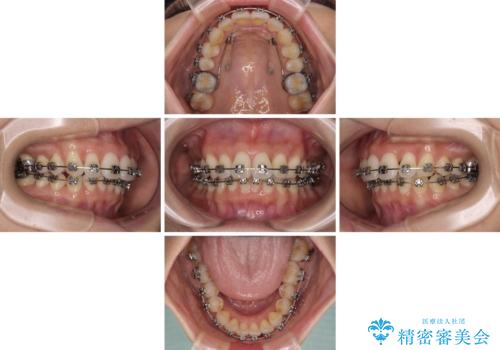

- 矯正装置

- メタルブラケット

- 治療期間

- 1年11ヶ月

アンカースクリューと補助装置を使用して上顎大臼歯を遠心移動させることで咬み合わせを改善し、ワイヤー装置によりデコボコを解消しながら口元の突出感も改善していくこととしました。